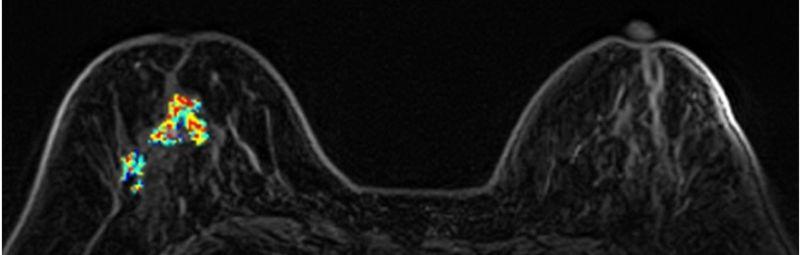

(3)乳房MRI磁力共振造影檢查:

無輻射、高解析度、無痛的高階影像檢查,對偵測腫塊病灶有極高的敏感度,是極佳的診斷利器。適用有乳癌家族史、曾罹患卵巢癌及子宮內膜癌者、帶有特定家族遺傳基因(BRCA1、BRCA2等),或曾接受乳房手術的女性(如自體脂肪豐胸、假體植入、矽膠注射隆乳),建議至少每兩年一次MRI檢測,除偵測早期乳癌外,同時可評估植入物之完整性。

MRI對偵測腫塊病灶有極高的敏感度。

64歲石小姐,曾接受矽膠注射隆乳,因右乳疼痛求診,但矽膠在乳房攝影及超音波下會遮蔽病灶而無法診斷,經磁力共振造影MRI發現:右乳有一不規則腫塊(約55mm)、乳頭內縮,高度懷疑惡性腫瘤,經手術證實為乳癌。